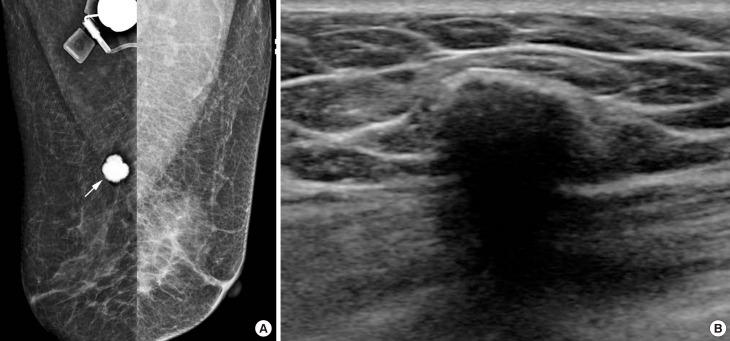

Osteosarcoma most commonly metastasizes to the lung or the skeleton, and metastatic osteosarcoma to the breast is very rare, with only a few cases reported. Due to its rarity, little has been reported about its imaging features. In this report, we represent a 58-year-old woman with metastatic osteosarcoma to the right breast from a tibial osteosarcoma. The imaging features of the metastatic osteosarcoma to the breast by using dedicated breast imaging modalities are described. Although rare, metastatic osteosarcoma to the breast should be considered when dense calcified masses with suspicious features are seen on breast imaging in patients with a history of osteosarcoma.

摘要

骨肉瘤最常转移至肺或骨骼,而骨肉瘤转移至乳腺极为罕见,仅有少数病例报道。由于其罕见性,关于其影像学特征的报道很少。在本报告中,我们介绍了一名58岁女性,其右乳腺的骨肉瘤转移灶来自胫骨骨肉瘤。描述了使用专用乳腺成像模式时乳腺转移性骨肉瘤的影像学特征。尽管罕见,但对于有骨肉瘤病史的患者,当乳腺成像中发现具有可疑特征的致密钙化肿块时,应考虑骨肉瘤转移至乳腺的情况。